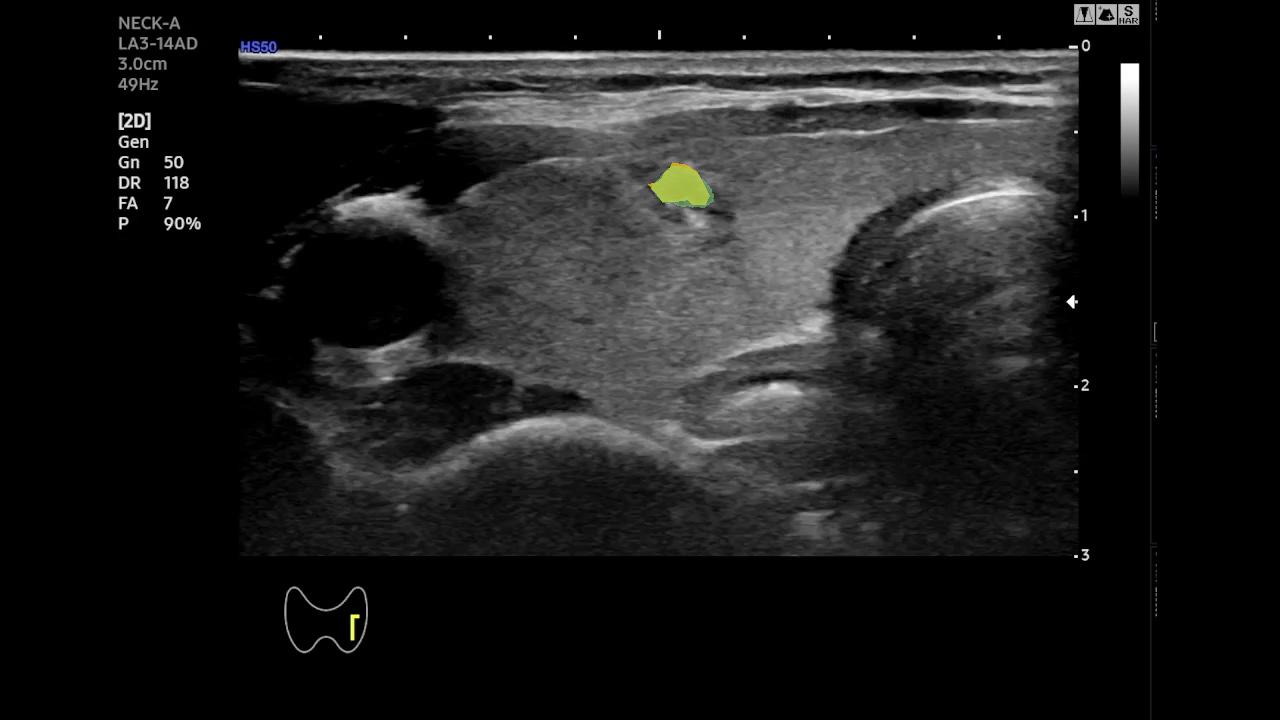

Qualitative Analysis of Temporal Stability- To better highlight the temporal behavior of SAM-2 and EMA-SAM, we visualize predictions at representative frames sampled from a complete RFA sequence. Figure 2 shows a three-row comparison: the first row displays the original ultrasound frames at selected timestamps (with ellipses indicating omitted intermediate frames), the second row shows SAM-2 predictions, and the third row presents EMA-SAM results. As the sequence progresses, SAM-2 occasionally loses the PTMC region when it becomes indistinct or is occluded by RFA bubbles, sometimes mis-segmenting nearby tissue. In contrast, EMA-SAM maintains a coherent segmentation trajectory throughout the sequence. Its confidence-weighted exponential-moving-average pointer preserves a robust latent prototype of the lesion, allowing rapid re-identification and boundary recovery once the PTMC reappears.

Original

SAM2

EMA-SAM